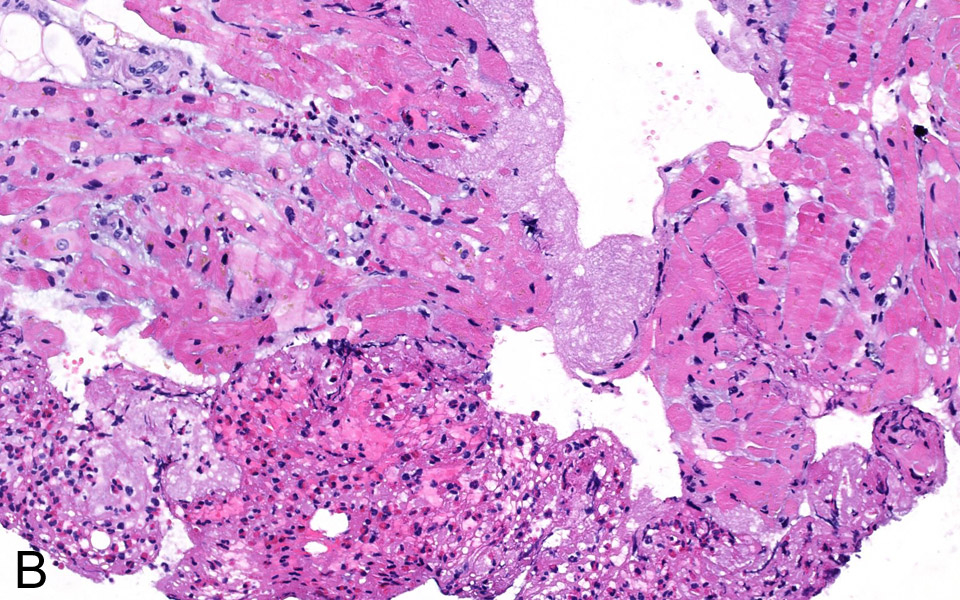

Figure 3B

Fibrinous thrombotic material mixed with numerous eosinophils was attached To the endocardium (H&E stain, 200x).